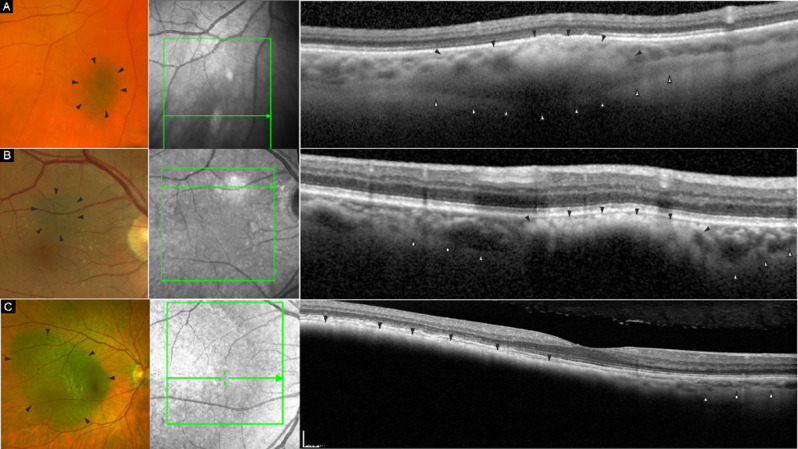

目的:评估高分辨率光学相干断层扫描(HR-OCT)与标准光谱域 OCT 在色素性脉络膜病变中的应用:我们共筛查了40名患有色素性脉络膜病变的受试者。我们用HR-OCT和标准OCT设备对病变部位进行了成像,包括增强深度成像(EDI)模式和非增强深度成像(EDI)模式。对图像进行定性和定量分级,如脉络膜压缩和宽度、脉络膜反射率和厚度等:结果:40 名受试者中有 32 名可以进行图像分析,其余受试者因成像不足而被排除在外。HR-OCT EDI模式可观察到11个病变(11/32 = 34.4%)的脉络膜后部范围,而正常HR-OCT(n = 32)、标准OCT(n = 30)和OCT EDI模式(n = 30)分别有6个病例(6/32;18.8%)、4个病例(4/30;13.3%)和5个病例(5/30;16.7%)可观察到脉络膜后部范围,尽管差异不大。10例患者在HR-OCT上出现明显的绒毛膜压缩,在所有成像模式下同样可见。平均绒毛膜厚度为 11.6 至 13.9 微米(标清范围为 3.84 至 4.33),压缩的绒毛膜厚度同样为平均 7.1 至 7.8 微米(标清范围为 2.20 至 3.55)。在四种模式中,有三种模式的图像质量向周边明显下降(p = 0.0077 至 p = 0.29):结论:HR-OCT可以更好地显示色素性脉络膜病变中的视网膜和脉络膜结构,但在尝试对周边病变成像时,图像质量会下降:HR-OCT原型可深入了解色素性脉络膜病变的临床特征,而这些特征在传统的OCT成像中并不明显。这支持了HR-OCTolution OCT设备的开发。

Methods: We screened a total of 40 subjects with pigmented choroidal lesions. Lesions were imaged on HR-OCT and standard OCT devices with and without enhanced depth imaging (EDI) mode. Images were graded for qualitative and quantitative aspects, like choriocapillaris compression and width, choroidal reflectivity and thickness, amongst others.

Results: 32 of the 40 subjects could be included in the image analysis, the rest were excluded due to insufficient imaging. HR-OCT EDI mode allowed visualization of the posterior choroidal extent in 11 lesions (11/32 = 34.4%) versus in six (6/32; 18.8%), four (4/30; 13.3%), and five cases (5/30; 16.7%) in normal HR-OCT (n = 32), standard OCT (n = 30) and OCT EDI mode (n = 30), respectively, albeit not significantly different. Choriocapillaris compression was evident in 10 cases on HR-OCT and equally visible in all imaging modes. Mean choriocapillaris thickness ranged from 11.6 to 13.9 microns (SD range 3.84-4.33), and compressed choriocapillaris thickness similarly ranged from a mean of 7.1 to 7.8 microns (SD range 2.20-3.55). Image quality declined significantly towards the periphery in three out of four modes (p = 0.0077 to p = 0.29).

Conclusions: HR-OCT may provide better visibility of retinal and choroidal structures in pigmented choroidal lesions, although image quality is reduced in attempting to image peripheral lesions.

Translational relevance: The prototype HR-OCT offers insights into clinical features of pigmented choroidal lesions that are not apparent on conventional OCT imaging. This supports the development of HR-OCTolution OCT devices.